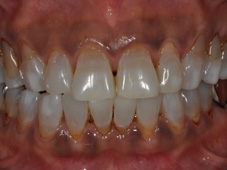

ホワイトニングの例

ケース1:40歳代の女性で、元々の歯の色の濃い方でしたが、2か月のホームホワイトニングと3回のオフィスホワイトニングで、こんなに白くなりました!

⇒

(写真は同じ設定で撮影しており、画像処理を行っていません)